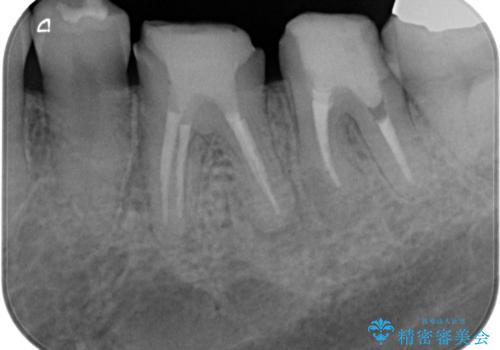

- 銀歯・虫歯・治療途中の歯を治していきたい、セラミックの歯にしたい!と希望され来院されました。

銀歯の下で再発した虫歯や、根尖病変等、多々の問題が認められましたがひとつづつ丁寧に改善し、長期的な予後の見込めるセラミック治療を行っていきます。